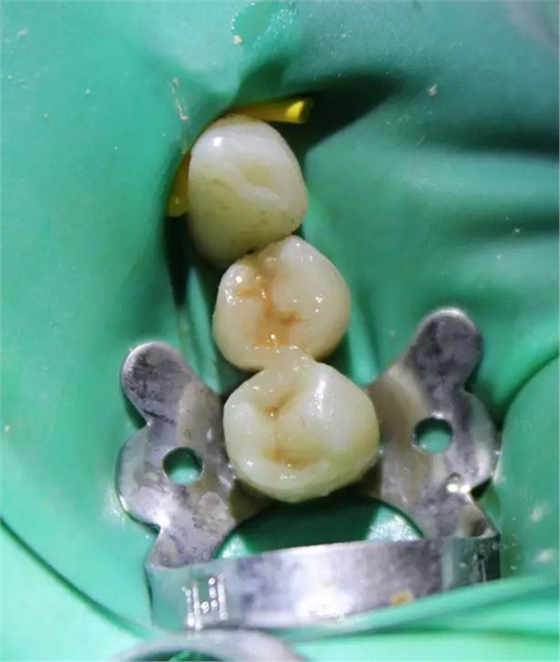

圖6 左下4和左下5使用瓷納美通用修復型樹脂及SDR修復后的效果。